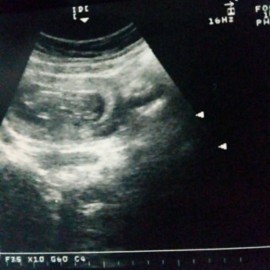

Ada yg sama ga bunda2 saya hamil 18 week tpi perutku kecil.USG waktu usia 13 week ada yg tau ga